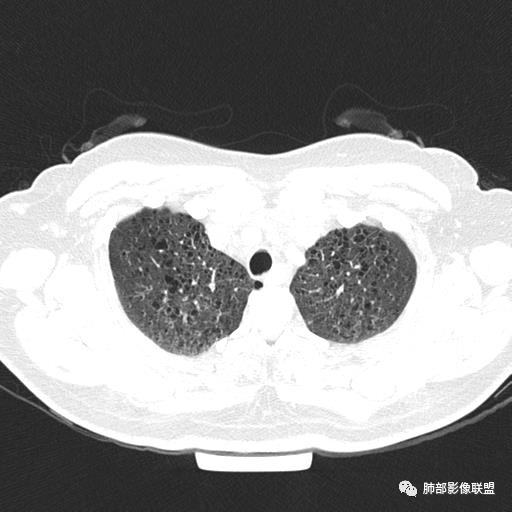

双肺弥漫囊腔,累及肋膈角,囊腔形态相对规则单一。

CT平扫示双肺弥漫分布大小不等囊状薄壁透光区,无内、中、外带分布差异,间质稍示增厚。拟LAM

中年女性育龄期妇女,咳嗽气喘,无吸烟史,有苯吸入史。影像:双肺弥漫均匀小囊腔,无明显分布优势,囊腔形态欠规则,壁薄,部分囊腔边缘血管征,伴双肺弥漫磨玻璃影,无结节,考虑lam,鉴别苯中毒肺损伤,囊腔多有分布优势,小叶中心分布为主,形态规整等

女,46,活动性气喘1年。苯吸入史半年。胸部CT:两肺弥漫囊腔,上至肺尖,下至肋膈角,形态类似小囊腔。考虑:LAM,鉴别LIP,BHD,PLCH等。

双肺弥漫大小不一薄壁含气囊腔,囊间肺组织正常,正常肺背景,肺尖肺底受累;青年女性,气喘,支持LAM

CT表现:双肺弥漫大小不等的薄壁囊腔,囊壁<2mm,外形规则,血管影多位于囊腔周围,囊腔之间肺组织正常,随着疾病进展到晚期,囊腔变大、增多,不可胜数,囊腔可融合成较大的囊,与肺气肿相似,形成间质性肺纤维化。部分病例可出现结节影。